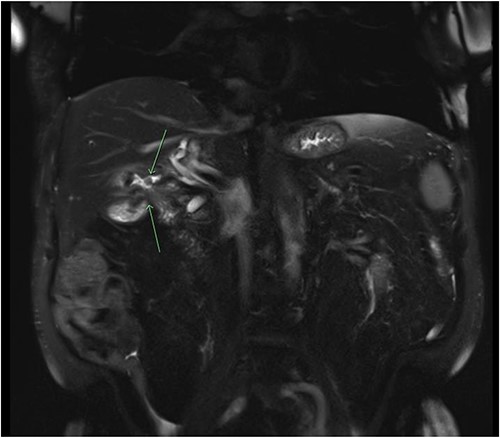

Consequently, a barium swallow and MRI abdomen were completed demonstrating the fistula between the first part of the duodenum and the ascending colon below the hepatic flexure (Figs 1 and 2). Surgical opinion and management of the patient was then sought. A subtotal cholecystectomy, partial duodenectomy, and partial resection of the colon was completed to excise the fistulous tracts. Given the patients age, he was sent to the intensive care unit for further monitoring. Day 3 postoperatively, the patient had ongoing pain and developed new tachycardia, and CT at this time demonstrated an obstruction at the colonic suture line. The patient was taken back to the operating room and a completion right hemicolectomy was performed. Histopathology from the original operation demonstrated heavy mucosal inflammation with a fistula identified histologically. The patient recovered relatively well and was able to be discharged home. The patient remained healthy and continued to be living independently in the community at 6-month follow-up.

Coronal slice of a magnetic resonance cholangiopancreatography (MRCP) with IV gadolinium demonstrating an abnormal fistulous connection between the contracted small calibre gallbladder and the colon just below the hepatic flexure; there is evidence of a second fistulous tract between the gallbladder and the duodenum.